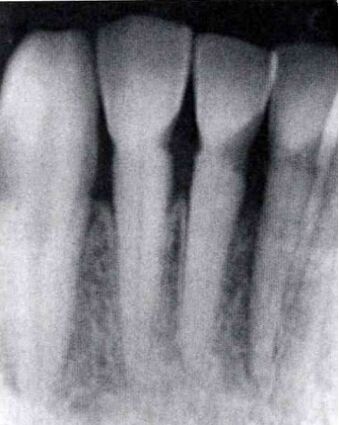

68.附圖X光片中,左下門齒有何形態異常? (A)雙生齒(gemination) (B)融合齒(fusion of teeth) (C)連合齒(concrescence) (D)巨齒症(macrodontia)